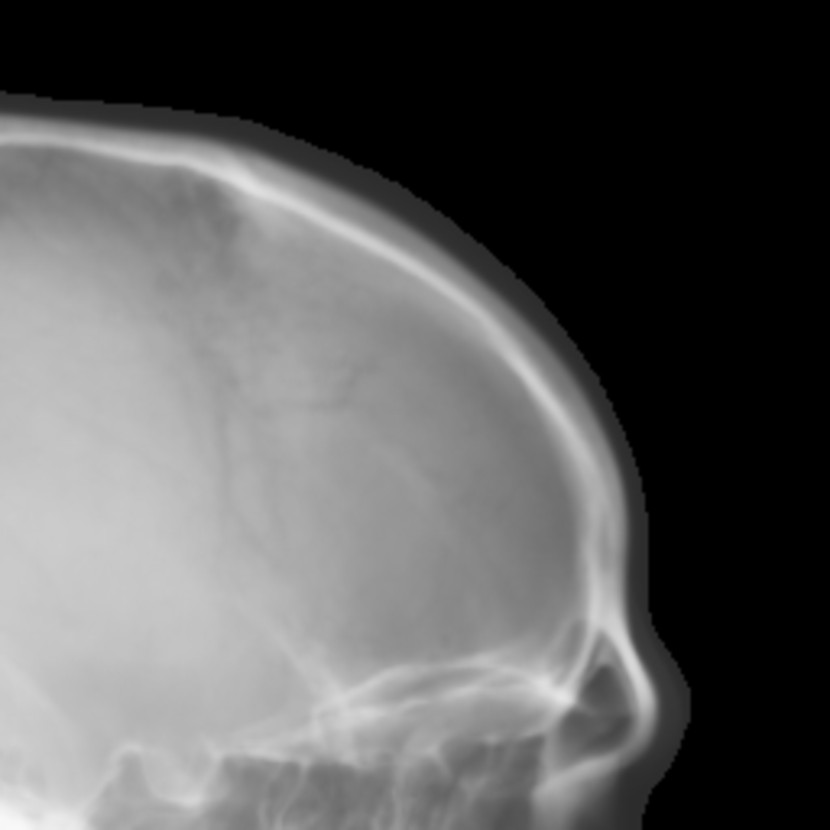

Refer to caption

(a) Real cephalogram

(b) Synthetic cephalogram

(c) Plot of samples and sigmoid curves

Fig. 2: Image contrast difference between real conventional cephalograms and RayCast synthetic cephalograms: (a) a real cephalogram example; (b) a RayCast synthetic cephalogram example; (c) the plot of samples between RayCast synthetic cephalograms and real cephalograms with an original sigmoid curve (red) and our proposed modified sigmoid curve (blue).

In Fig. 2, one real conventional cephalogram example and one example of 𝒈𝒈\boldsymbol{g} are displayed, where evident image contrast difference between these two images is observed. It is because the X-ray films used in conventional cephalograms have the special nonlinear optical property that the characteristic curve between optical density and logarithmized X-ray exposure has a sigmoid-like shape [42]. According to the Lambert-Beer law, the logarithmized X-ray exposure is equivalent to the attenuation integral. It indicates that the intensity relation between the desired cephalogram and the attenuation integral image 𝒈𝒈\boldsymbol{g} should also exhibit a sigmoid-like curve. Therefore, to make the image contrast of synthetic cephalograms similar to conventional cephalograms, a sigmoid intensity transform is necessary.